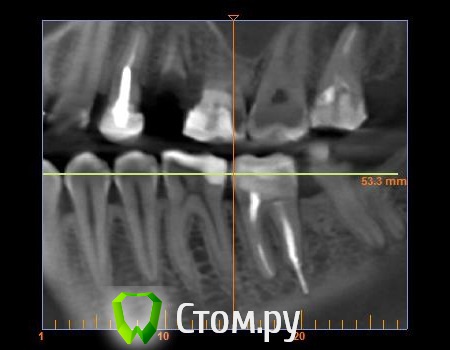

mastermind Опубликовано 22 августа, 2014 Автор Поделиться Опубликовано 22 августа, 2014 Нарезал 3 картинки из КТ Ссылка на комментарий